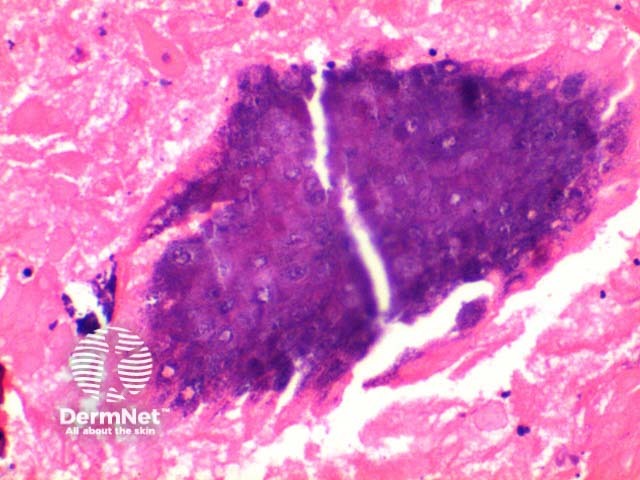

At low power the histological pattern seen in pilomatricoma is of a well-circumscribed nodulocystic tumour (Figure 2). While predominantly seen within the lower dermis, extension into the subcutaneous tissue is not uncommon. The tumour is comprised of a basaloid proliferation resembling the hair matrix cells, which matures into structureless eosinophilic cells lacking nuclei called shadow cells (Figures 3 and 4). The shadow cell area represents differentiation towards the hair cortex. Frequently there are areas of calcification within the shadow cell regions (Figure 5). A histiocytic infiltrate with multinucleated cells forms at sites of rupture (Figure 6).

Figure 4

Figure 5